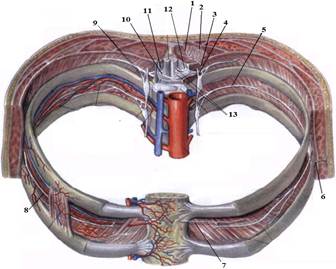

1. Яким номером позначено N. thoracicus?

2. Яким номером позначено N. intercostalis?

3. Яким номером позначено R. cutaneus lateralis?

4. Яким номером позначено R. dorsalis n. thoracici?

5. Яким номером позначено R. cutaneus lateralis r.dorsalis n. thoracici?

6. Яким номером позначено R. cutaneus medialis r.dorsalis n. thoracici?

7. Яким номером позначено R. cutaneus anterior?

8. Яким номером позначено Rr.communicantes n. thoracici?

9. Яким номером позначено Radix dorsalis n. thoracici?

10. Яким номером позначено Radix ventralis n. thoracici?